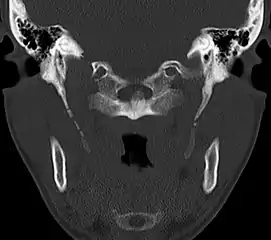

CT scan, coronal section showing bilateral extended styloid process and stylohyoid ligament ossification (incidental finding)